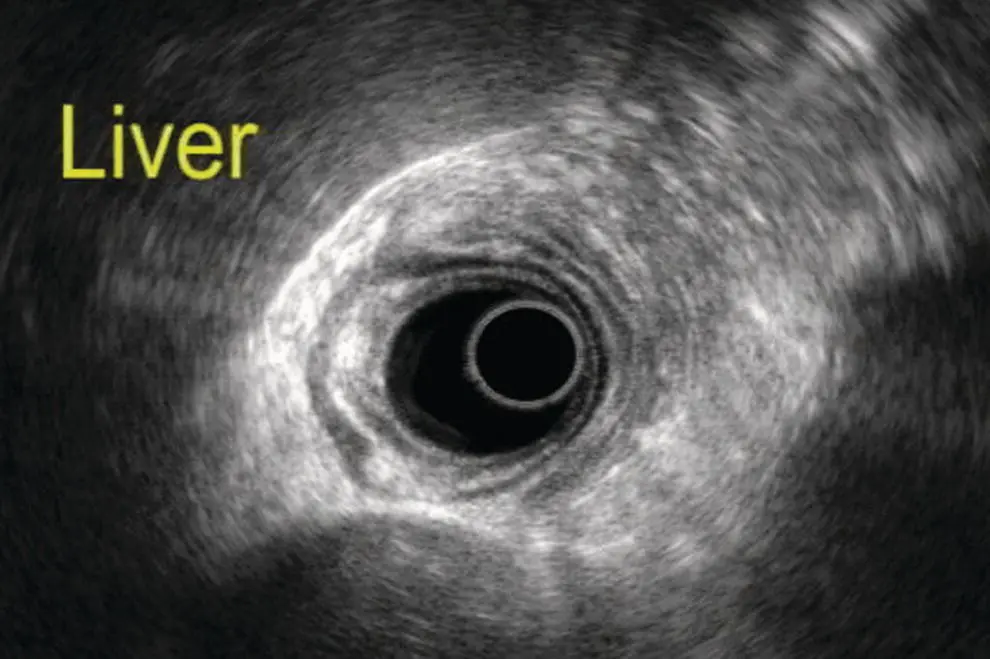

Radial endosonography

As the radial probe is advanced through the esophagus into the gastric cardia, the liver is the predominant organ visualized. When positioning the abdominal aorta at the 6 o’clock position, the left lobe of the liver is seen anteriorly and medially to the right ( Figure 7.1). The aorta, with a dark hypoechoic band which is the diaphragmatic crux, is seen immediately adjacent to the probe. In this position, near the hiatus, the hepatic veins are seen as anechoic structures, entering the inferior vena cava (IVC). In this position, possibly with left tip deflection, the spleen can be seen on the right of the screen. As the aorta is traced distally, maintaining its 6 o’clock position, the liver may still be seen anteriorly. Vascular structures can be differentiated from ductal structures by a thicker (echogenic) wall and the presence of flow.

Figure 7.1 Image of the liver scanned by radial ultrasound.